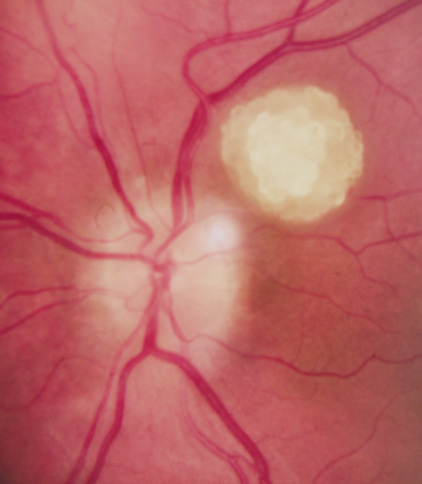

SEIZURES. Typically observed first in infancy, seizures are a common presenting sign of TSC and a frequent source of morbidity. The seizures often begin as “salaam spasms”—repetitive myoclonic spasms that produce head nodding with associated extension/flexion of the trunk and limbs. They often progress to grand mal seizures25,116 and may be difficult to control. Vigabatrin has been advocated for control of infantile spasms but it carries a risk for irreversible visual field loss. Other treatments include corticosteroids, adrenocorticotrophic hormone, and a ketogenic diet.25,137–139 Selective surgical excision of an “epileptogenic tuber” may be an option for intractable epilepsy.140 MENTAL RETARDATION. Mental deficiency, part of Vogt's diagnostic triad (adenoma sebaceum, epilepsy, mental deficiency),3 affects about 50% of patients overall.25,141 TSC2 mutations may carry a higher risk than TSC1.142 AUTISM. This may affect 50% to 60% of TSC patients, possibly correlating with numbers of cerebellar and temporal tubers.25,143,144 Visceral Findings Patients with TSC may have renal, cardiac, pulmonary and other visceral involvement. RENAL. The TSC2 gene was localized by linkage with the polycystic kidney disease gene in patients with TSC and polycystic kidneys. This represents a contiguous gene syndrome in which adjacent genes (PKD1 and TSC2) are deleted together.145–147 Multiple angiomyolipomas of the kidney are benign hamartomas of blood vessels, smooth muscle, and fat. By 10 years of age, the frequency of angiolmyolipomas is 75%, similar to adults.148 The fat signal of angiomyolipomas helps to distinguish them from renal cell carcinoma.25 Renal insufficiency/failure may be the complication of both cystic disease and angiomyolipomas and is one of the leading causes of morbidity and mortality in TSC.138,149 CARDIAC. Rhabdomyoma are usually multiple, typically asymptomatic, and often regress with age.150,151 PULMONARY. Lymphangioleiomyomatosis is a progressive lung disease characterized by bronchiolar smooth muscle infiltration and cystic changes of the lung parenchyma. About 1% of adult females with TSC are affected.116,152,153 OPHTHALMIC FEATURES The principal ophthalmic manifestations of TSC are in the posterior segment. Astrocytic Retinal Hamartomas Although in Van der Hoeve's original description the term phakoma or phakomata was a generic term for the tumors occurring in various organ systems,1 it has become associated with the retinal astrocytic tumors of TSC,3 which occur in about 50% of affected patients and are bilateral in 25% to 30% (Table 3, Fig. 16).154,156

Historically, the presence of mixed (type 3) hamartomas led to the suggestion of evolution from the type 1 to the type 2.157 A long-term photographic study found that although the types remained unchanged, a minority of types 1 and 3 increased in calcification and a new lesion was noted that had not been evident on an earlier photograph.157 All three types of retinal hamartomas may be found in young children. There is no correlation between age and the predominant type of lesion.156 Histologically, phakomata are composed of glial astrocytes—elongated, fibrous astrocytes with small oval nuclei, arising from the retina or the optic disc. The type 2 lesions contain basophilic, calcified drusen-like deposits within a dense vascular network. On fluorescein angiography, the type 2 lesions show autofluorescence, leakage with transit of dye, and marked late hyperflorescence.3,113 Astrocytic retinal hamartomas usually do not affect vision and require no treatment. Vitreous seeding and vitreous hemorrhage have been reported in association with phakomata, but these are rare.158,159 Laser photocoagulation may be considered in rare cases were exudation induces serous retinal detachments.160 The differential diagnosis of “white retinal lesions” includes retinoblastoma, toxoplasmosis and toxocara.3,113 Pigmentary Abnormalities Depigmented “punched-out” chorioretinal lesions in the midperiphery have been reported in up to 40% of patients. Similar lesions may be found in normal patients.156 Nonretinal Features The adnexae may be involved by angiofibromas: eyelid skin and “salmon-colored” subconjunctival nodules. Sector iris depigmentation and iris coloboma have been reported in a minority of patients.113,156,161 DIAGNOSTIC CRITERIA When TSC is classical (“Salaam seizures,” facial angiofibroma, developmental delay), the diagnosis is straightforward. However, children can be mildly affected, and many of the classical signs may become apparent later. Based on the revised clinical diagnostic criteria set forth by the Tuberous Sclerosis Consensus Conference162, a diagnosis of TSC may be made if the patient has two major features, or one major feature plus two minor features. Genetic testing for TSC still has a high false-negative rate (Table 4).25,162,163 TABLE 4. Features of Tuberous Sclerosis Complex